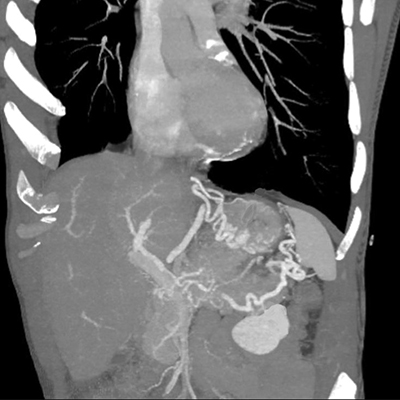

An abdominal computed tomography (CT) scan with portal phase was performed, showing dilatation of the caudal pancreatic duct (Figure 1) along with splenic vein thrombosis and gastro-epiploic and fundus varices (Figure 2).

Figure 2

CT performed during portal phase, Maximum Intensity Projection 3D-reconstruction showing splenic vein thrombosis with subsequent gastro-epiploic and fundus varices.